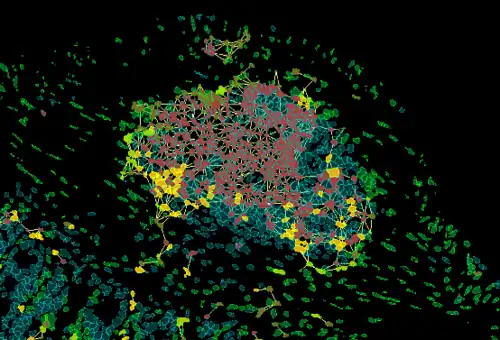

The integration of AI and machine learning has been instrumental in the development of tissue cytometry. For instance, AI-driven algorithms can be trained to identify specific cell types, detect subtle morphological changes associated with disease, or quantify the density of immune cells within a tumor microenvironment.[12]

By precisely delineating individual nuclei, researchers can extract valuable information about nuclear size, shape, and texture, which can be correlated with various pathological conditions. Similarly, tissue segmentation algorithms enable the identification of different tissue compartments, such as tumor, stroma, and immune infiltrate, facilitating the analysis of spatial relationships between cellular components.[13]

Tumor Microenvironment: Tissue cytometry is heavily used in research to characterize the tumor microenvironment including e.g. identification of the immune landscape or tumor-vascularization, within IHC/IF-processed tissue sections. One reason is that by using this technology the complex tissue architecture stays intact and therefore also spatial relationships between cellular phenotypes and/or multicellular structures can be analyzed.[14]

By utilizing tissue cytometry multiple research groups were able to demonstrate the impact of various immune cell subpopulations (CD4, CD68, CD8, CD20, Foxp3, PD1) on patient survival in different cancer types (e.g. breast cancer, colon cancer, gastric cancer, melanoma, non-small cell lung cancer).[14] Since in cancer therapy a novel treatment strategy is targeting immune checkpoints (molecules that inhibit the antitumoral immune reaction), the insights gained by tissue cytometry may help to find new target molecules/biomarkers as well as to determine the best treatment strategy for patients.[14]